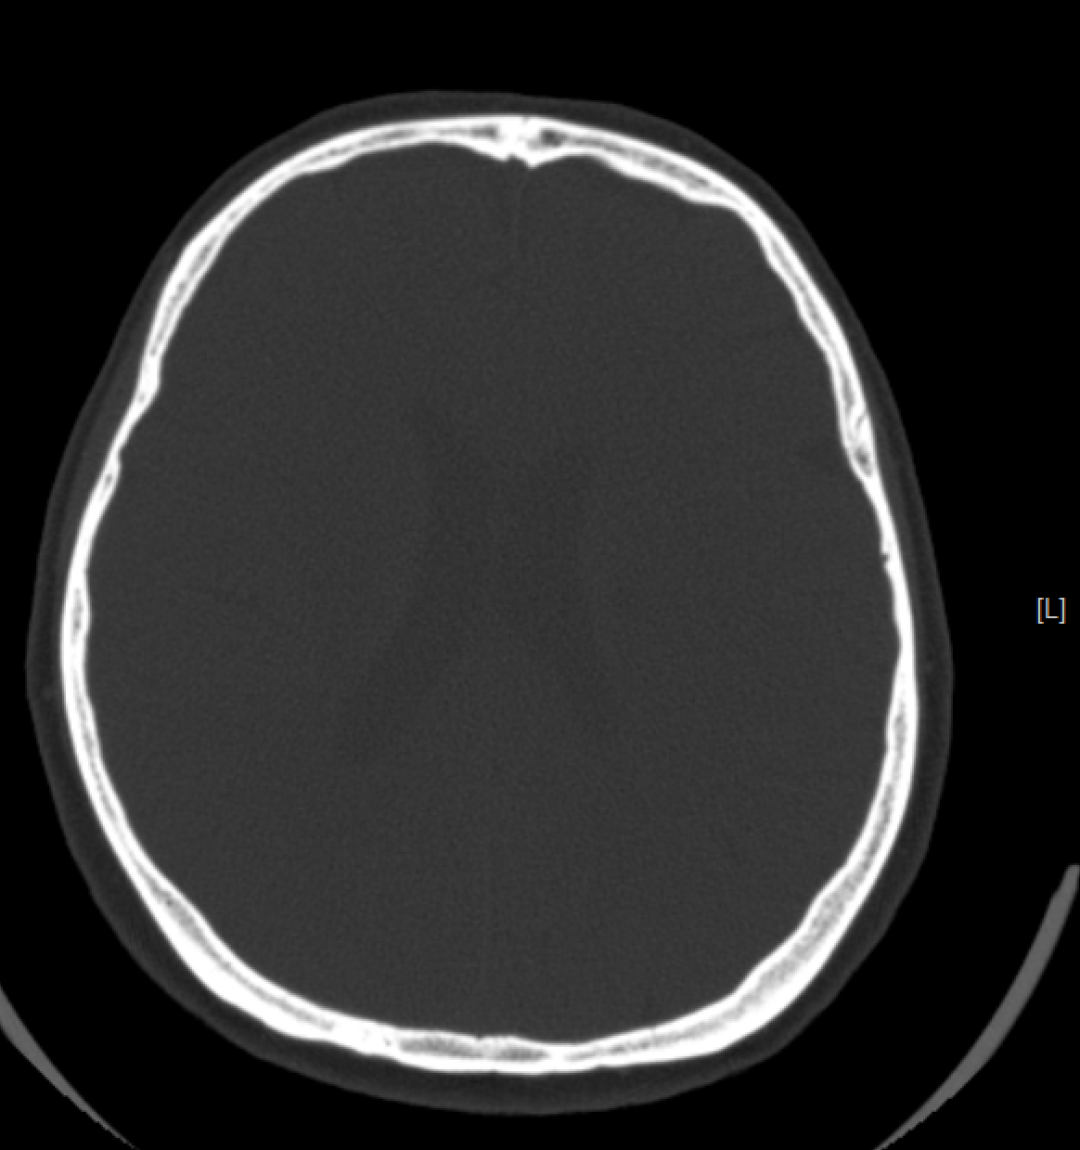

CT检查成像原理与DR类似,使用的是X射线,之后通过计算机成像。相较DR,CT可以多角度、多层面、多功能扫描成像,就像把一个面包切成多个平面进行观察。

检查应用范围:从头到脚,均可进行CT平扫,主要运用于头颅、颈部、胸部、腹部、脊柱、盆腔、四肢等部位。特别是高分辨率胸部CT,在检查肺部小结节时,运用非常广泛,CT检查脑出血也有相当的优势,另外微小的骨折、大部分器官的病变都能够看到。

优点:相较DR,CT的密度分辨率更高,可以显示DR检查不能发现或容易遗漏的病变。

而CT检查是把面包切片来看,获得的是真正的断面图像,没有层面以外的结构干扰。虽然细节看的更清楚了,但它就不是一块完整的面包了。